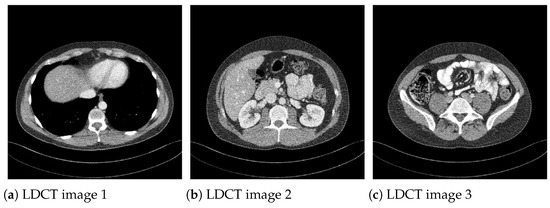

Moreover, to show the denoising performance of the proposed method on low-dose CT images, we used different noisy low dose (quarter-dose exposure images) abdominal CT images (Figure 4) from the 2016 NIH-AAPM-Mayo Clinic Low Dose CT Grand Challenge [30].

Figure 4. Low-dose (quarter-dose) abdominal CT medical images, 512 × 512 pixels.